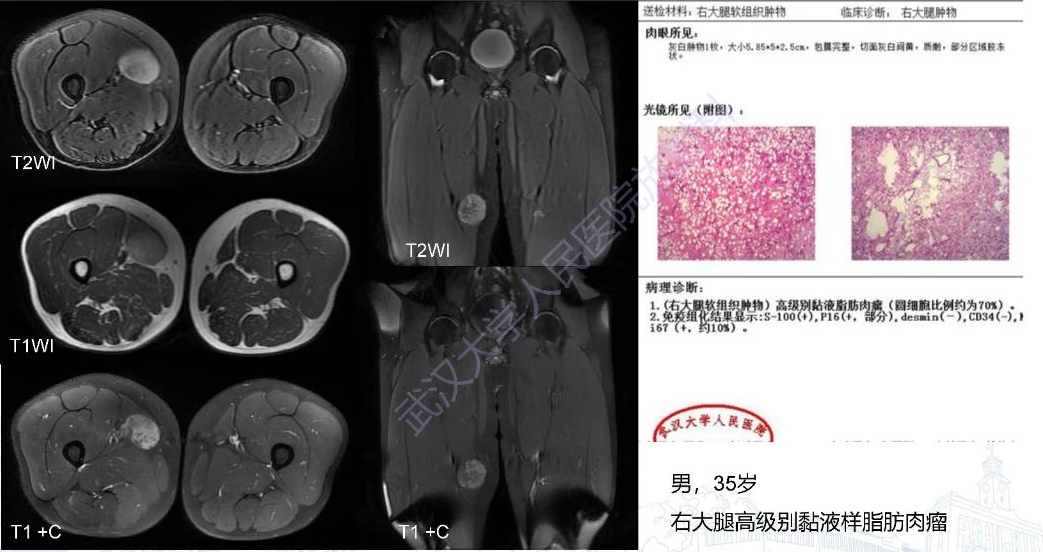

2.粘液样脂肪肉瘤: 肿瘤多边界清晰,瘤内多可发现脂肪成分,当脂肪含量少时较难鉴别。T2WI 表现为多个分叶状高信号肿块,无低信号间隔,增强扫描普遍表现为均匀或不均匀强化,而 EMC 主要表现为边缘强化和间隔强化,且粘液脂肪肉瘤一般没有钙化。